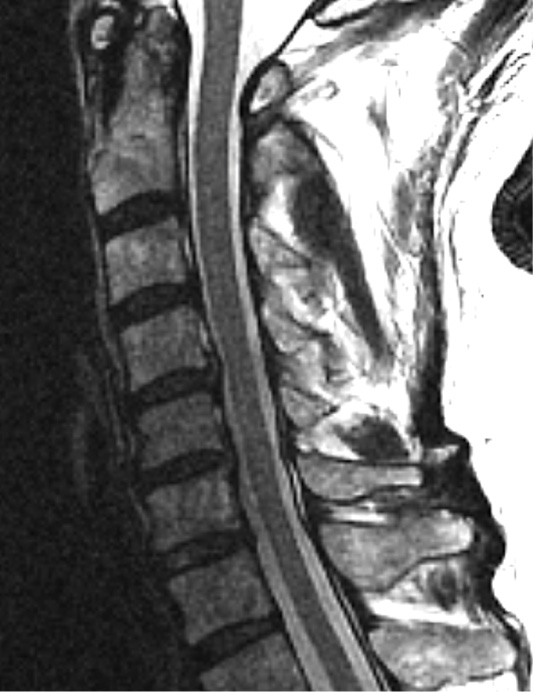

MRIs illustrated mild degenerative disc disease from C4-6 with disc herniations at both C4-5 and C5-6. The axial slice through C4-5 showed a right central disc herniation causing central and mainly right-sided foraminal stenosis. The axial slice through C5-6 showed a central disc herniation also causing central and mainly right-sided foraminal stenosis. The axial slice through C6-7 showed a left-sided disc herniation causing some left-sided foraminal stenosis, however, the patient did not demonstrate any left-sided symptoms.